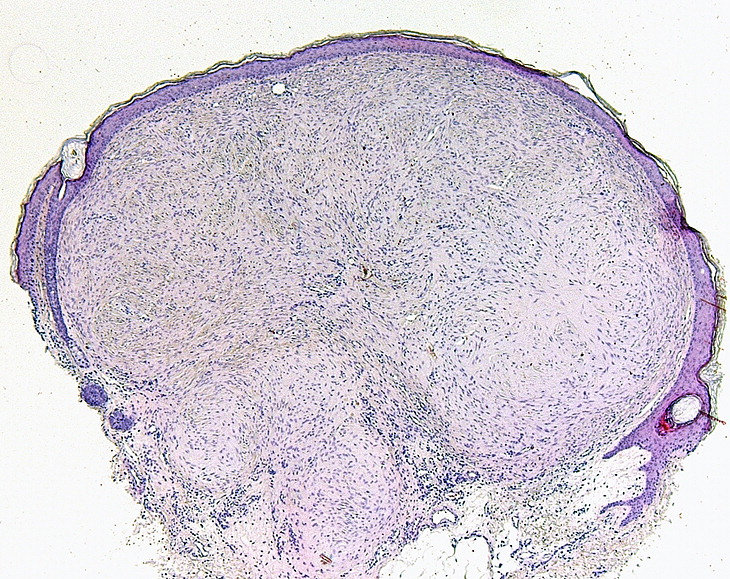

PA:Histologisch gaat het om bolvormige fibreuze tumoren

met een prominente vasculaire component, gelegen in de papillaire dermis. De

overliggende epidermis is atrofisch. Een haarfollikel kan aanwezig zijn in of

nabij de rand van de laesie. De oorspronkelijke naam trichodiscoma suggereert

dat de laesies uitgaan van de 'haardisk', maar daarover is twijfel. Daarom is

de naam discoid fibroma beter. Klinisch zijn het ook kleine ronde schijfvormige

oppervlakkig gelegen tumortjes. Een ‘haardisk’ werd in 1902 beschreven door

Pinkus als een mechanoreceptief adnexaal orgaantje, bestaande uit een schijf

rond de haar, rijk gevasculariseerd, waarin Merkelcellen en dikke gemyeliniseerde

zenuwuiteinden, en bekleed met een dikke epidermis.